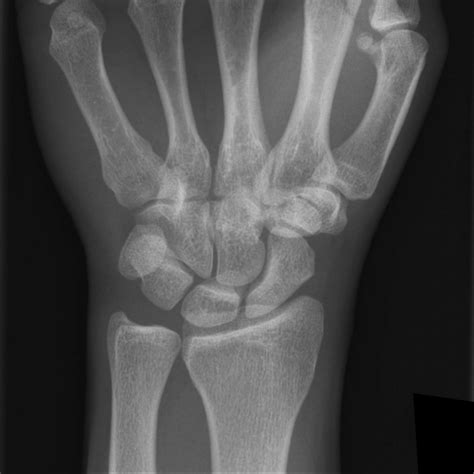

Normal Wrist X Ray PA Radiograph Of Normal Wrist | Download Scientific is a high-quality image in the Cleve collection, available at 1300 × 1081 pixels resolution — ideal for both digital and print use.

Understand the purpose and procedure of a wrist X-ray. Our guide explains how this diagnostic imaging tool identifies fractures, dislocations, arthritis, and bone injuries. Learn what to expect during your orthopedic exam, how radiologists interpret these medical images, and why this non-invasive test is essential for evaluating wrist pain and ensuring proper bone health recovery.